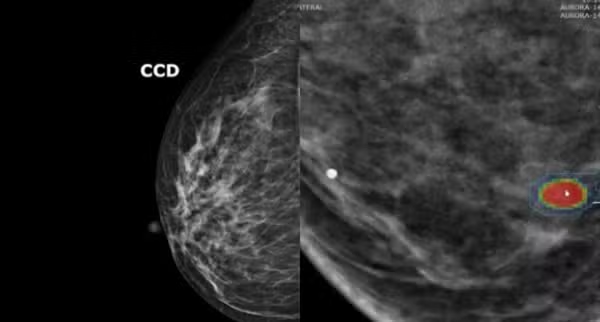

Agora um novo algoritmo promete reorientar a triagem: um modelo de inteligência artificial (IA) consegue avaliar com elevada precisão, simplesmente analisando dados de imagens de mamografia, o risco de uma pessoa desenvolver câncer de mama nos próximos cinco anos.

Ao contrário dos modelos de risco tradicionais, o algoritmo não requer informações sobre histórico familiar, genética ou estilo de vida. Ele calcula a probabilidade de câncer de mama exclusivamente a partir da mamografia e categoriza as mulheres em grupos de risco com base em limiares definidos.

A IA reconhece não apenas a quantidade de tecido glandular, mas também sua textura, o que é outro parâmetro para o risco de câncer de mama. “Apenas cerca de 10% das mulheres têm esse tecido glandular extremamente denso. A grande maioria das que desenvolvem câncer de mama e recebem um diagnóstico tardio têm tecido menos denso”, afirma Kuhl.

O avanço crucial, em sua opinião, é que “a IA pode decidir em segundos se uma mulher precisa ou não de uma ressonância magnética para detecção precoce”.